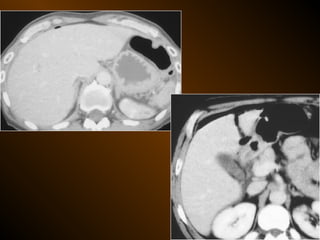

TỤ KHÍ NGOÀI PHÚC MẠC

• Nguyên nhân :

– Thủng tạng rỗng

– Áp xe tạo khí

• X quang quy ước

• Siêu âm

• XQCLĐT

TỤ KHÍ NGOÀIPHÚC MẠC • Nguyên nhân : – Thủng tạng rỗng – Áp xe tạo khí • X quang quy ước • Siêu âm • XQCLĐT